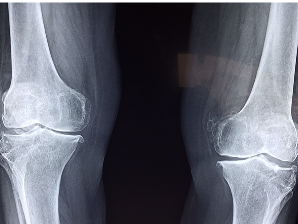

연골연화증은 연골 조직의 변성 및 파괴로 인해 발생하는 질환으로, 흔히 노인들이 걸리는 질병입니다. 주로 슬관절, 무릎관절, 척추 등 연골이 있는 곳에서 발생합니다. 연골 조직의 퇴행, 수분과 윤활제 감소로 인해 조직이 말라 뻣뻣해지거나 쉽게 부러질 수 있습니다. 이로 인해 관절 운동이 제한되거나 아픔을 유발할 수 있으며, 심각한 경우 관절염을 유발할 수 있습니다. 원인은 노화, 과도한 운동, 외상 등 다양합니다. 진단은 X선, CT, MRI 등의 영상검사로 확인됩니다.